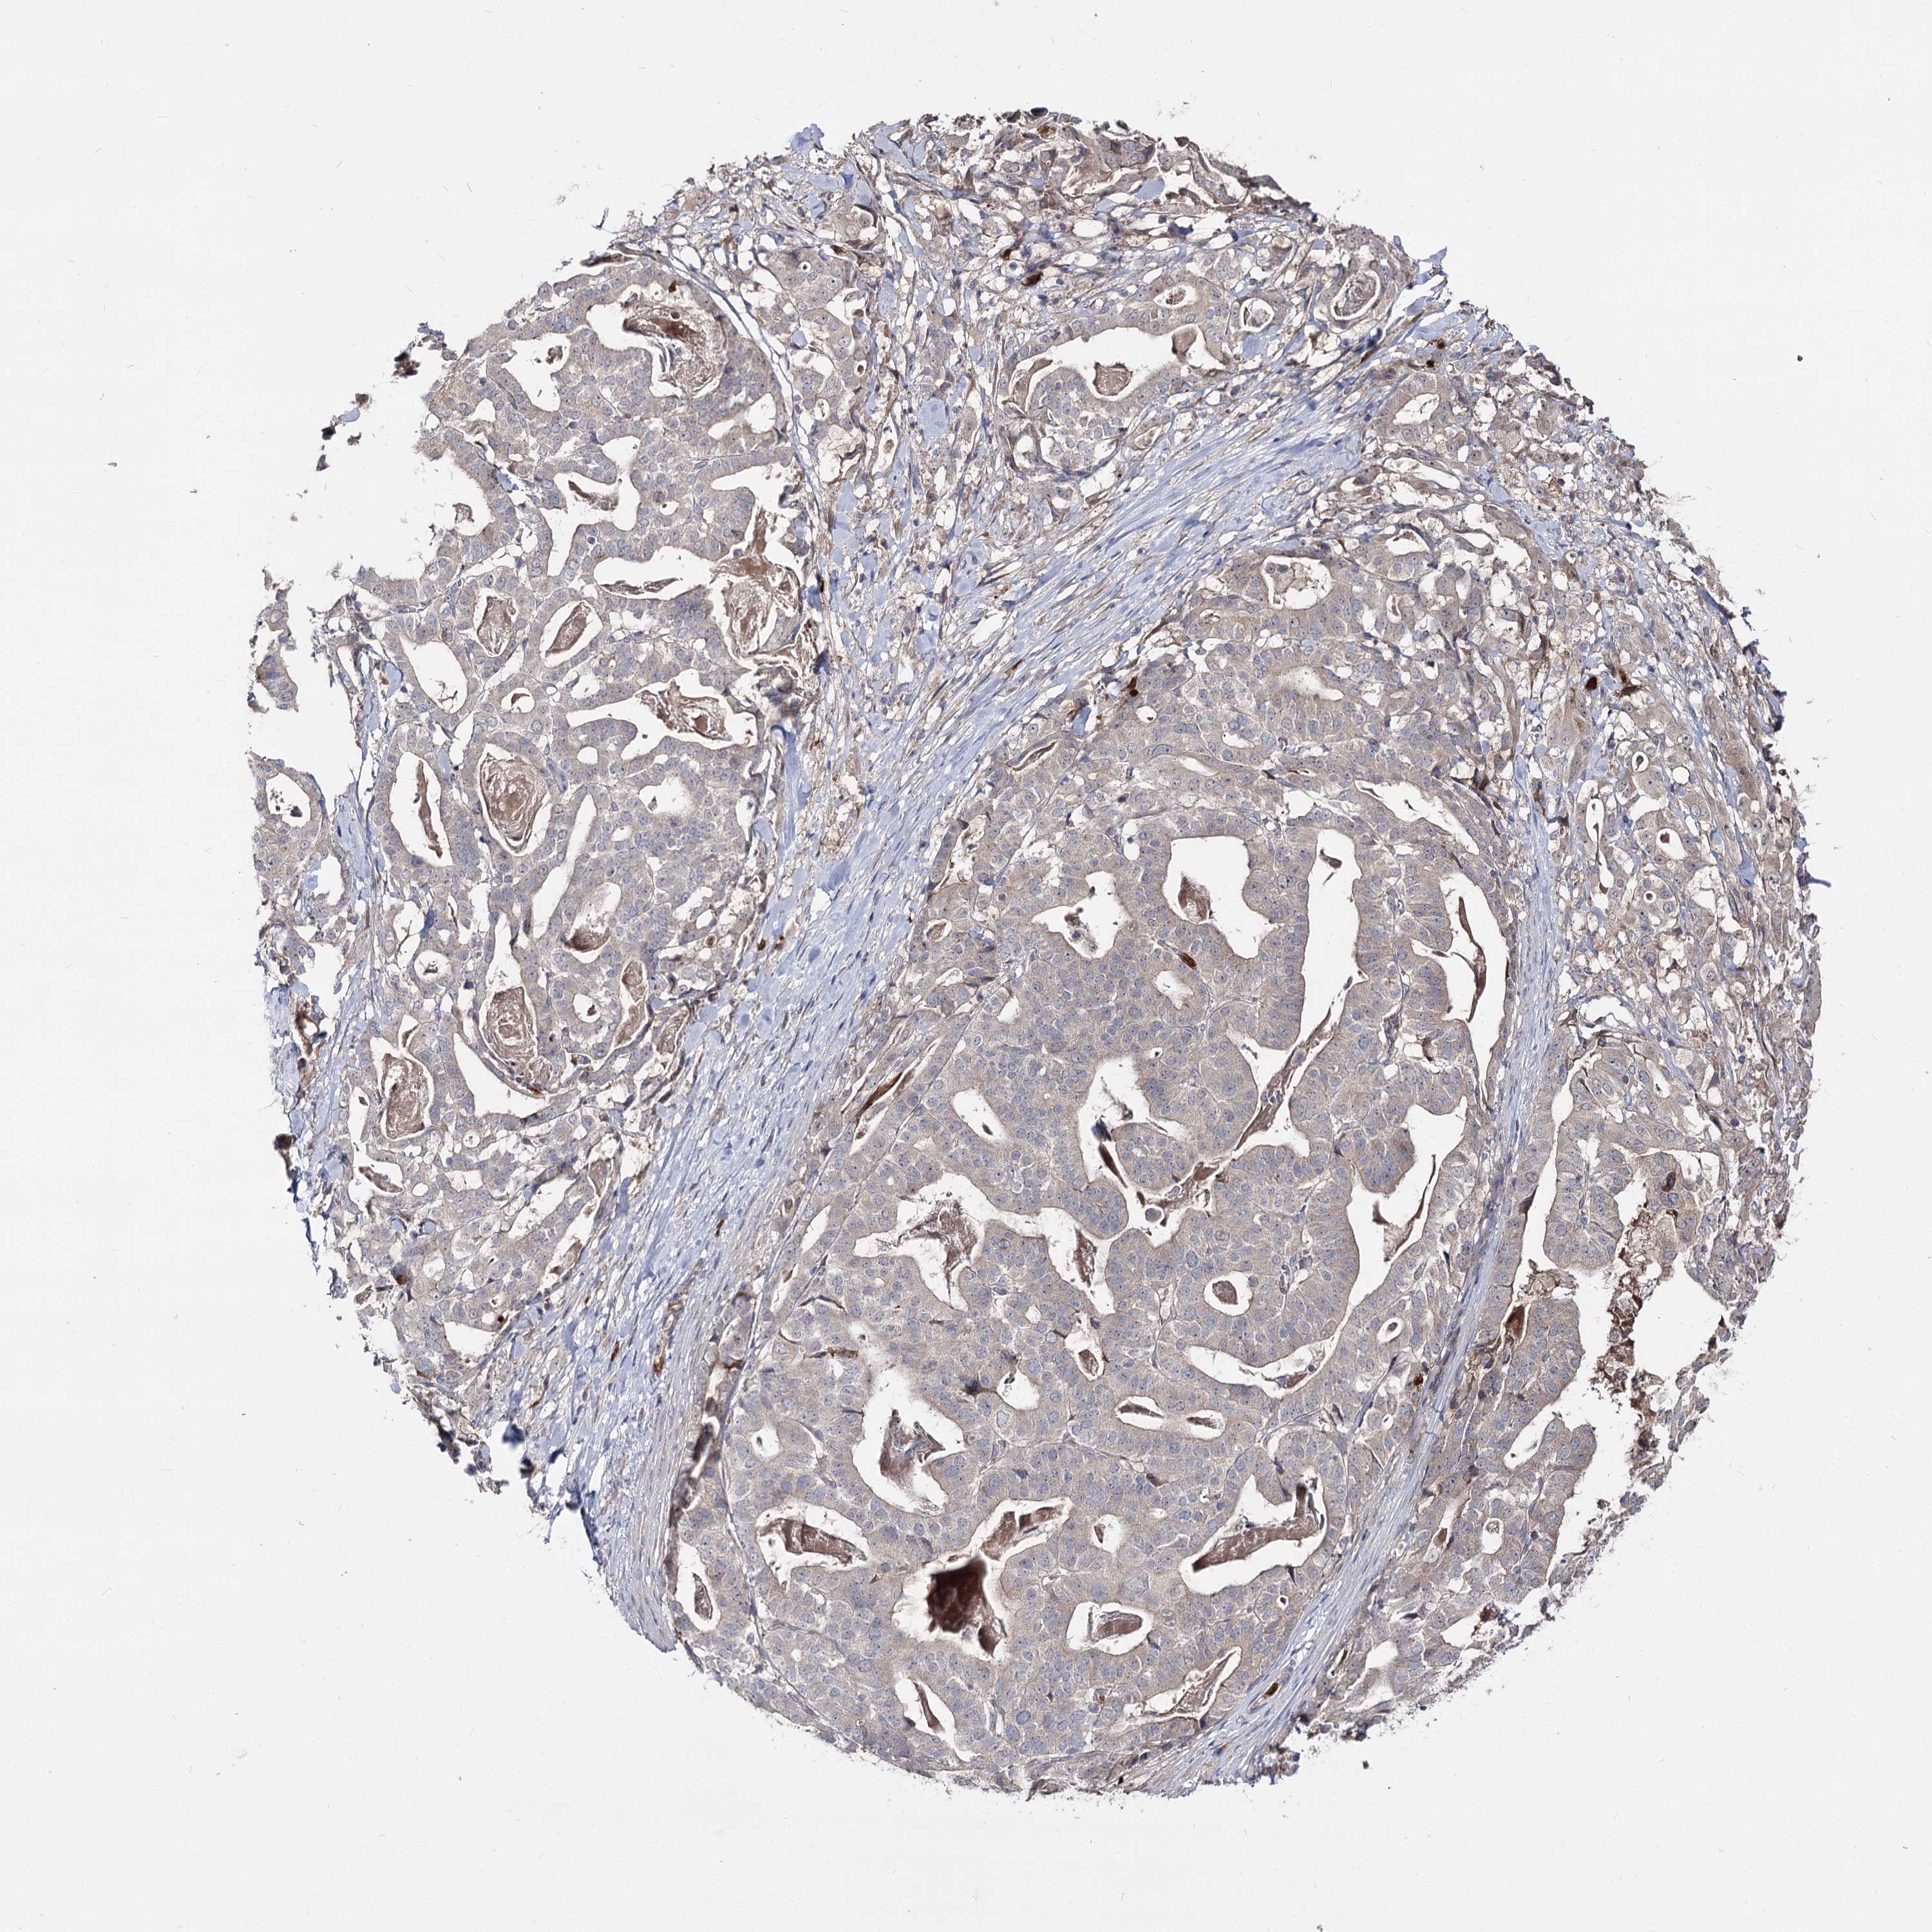

STOMACH CANCER - Protein expressioni

A mouse-over function shows sample information and annotation data. Click on an image to view it in a full screen mode. Samples can be filtered based on level of antibody staining by selecting one or several of the following categories: high, medium, low and not detected. The assay and annotation is described here.

Antibody stainingi

Antibody staining in the annotated cell types in the current human tissue is reported as not detected, low, medium, or high, based on conventional immunohistochemistry profiling in selected tissues. This score is based on the combination of the staining intensity and fraction of stained cells.

Each image is clickable and will lead to virtual microscopy that enables deeper exploration of all samples and also displays staining intensity scores, fraction scores and subcellular localization as well as patient and tissue information for each sample.

Antibody HPA038040

Staining

High

Medium

Low

Not detected

Intensity

Strong

Moderate

Weak

Negative

Quantity

>75%

75%-25%

<25%

None

Location

Nuclear

Cytoplasmic/membranous

Cytoplasmic/membranous,nuclear

Adenocarcinoma, NOS

Adenocarcinoma, High grade